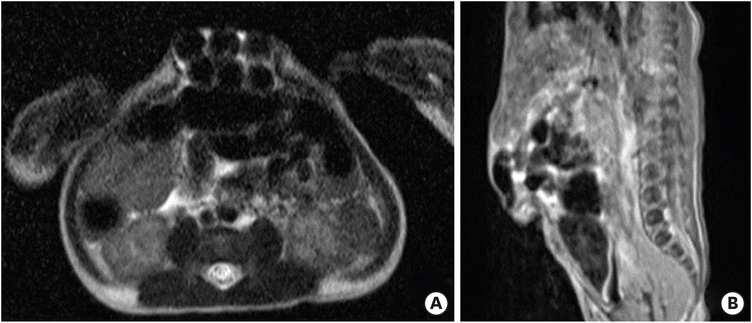

Fig. 5

Abdominal MRI.

MRI of the intestine showing a 4.3×2.5×1.5 cm hernia protruding in the anterior abdominal wall. It contains some portion of the small bowel and a part of the left liver. The subcutaneous fat is thin and abdominal wall muscle over the lesion is absent. There is no definite evidence of incarceration. (A) Axial view and (B) sagittal view.

MRI, magnetic resonance imaging.